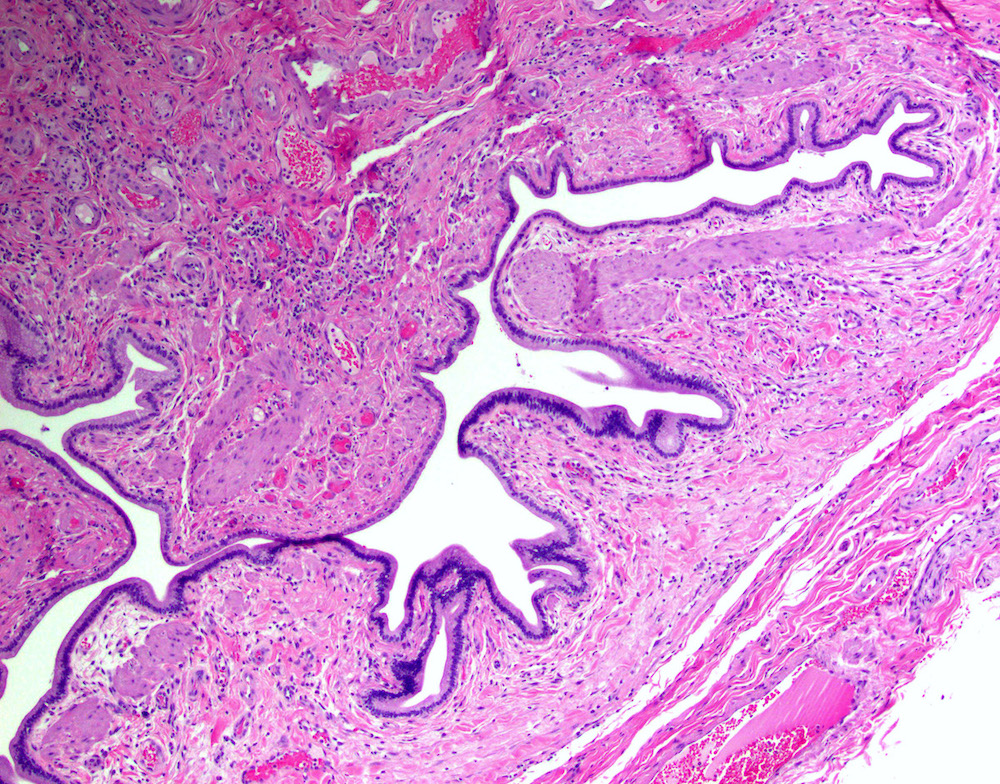

Microscopic (histologic) description

- Cystically dilated benign biliary glands accompanied by smooth muscle hypertrophy of gallbladder wall, thickened / fibrotic subserosa (StatPearls: Adenomyomatosis [Accessed 26 January 2021])

- Glands are distinct from the Rokitansky-Aschoff sinuses, which are epithelial diverticula, usually multifocal and occur throughout gallbladder secondary to injury, versus adenomyomatous nodule (distinct localized lesion of the gallbladder wall, 1 - 1.5 cm mural nodule in the fundus) (Am J Surg Pathol 2020;44:1649)

- May have reactive epithelial changes, papillary change and intestinal metaplasia (StatPearls: Adenomyomatosis [Accessed 26 January 2021])

- Rarely, benign glands are seen in proximity to nerves, appearing as perineural and intraneural invasion only in the subserosal layer (benign gland-like structures may migrate into nerves due to chemotactic factors or signaling substances with activation of cell receptors) (Am J Surg Pathol 2007;31:1598)

- Adenomyomatous nodules may rarely show dysplastic / carcinomatous transformation, whereas dysplasia in Rokitansky-Aschoff sinuses appears to be more common; however, the true association between adenomyomatous nodules and neoplasia has not yet been determined (Am J Surg Pathol 2020;44:1649)

- Recently, papillary dysplastic lesions of adenomyomas have been identified (intracholecystic neoplasms of adenomyomas), demonstrating cystic and solid areas with papillary projections that show biliary, gastric and intestinal phenotypes, with low or high grade dysplasia (Am J Surg Pathol 2020;44:1649)

Microscopic (histologic) images

Contributed by Monica T. Garcia-Buitrago, M.D.